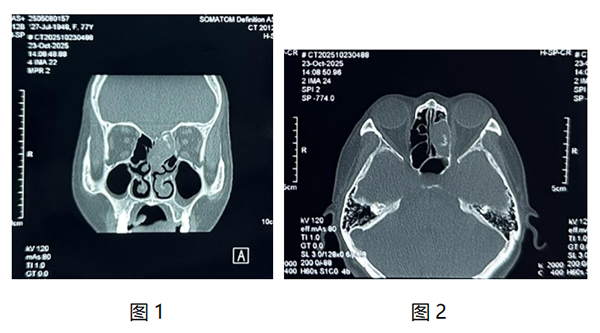

我院耳鼻咽喉头颈外科近日为一名77岁老年患者实施鼻内镜下筛窦开放+窦内病变清除术,患者因“左侧头痛多涕1月”到我院检查,入院查体可见左侧鼻腔中鼻甲水肿,上鼻道大量棕黄色干痂。鼻窦CT检查可见左侧筛窦内软组织影,内部密度不均。(如图1、2)